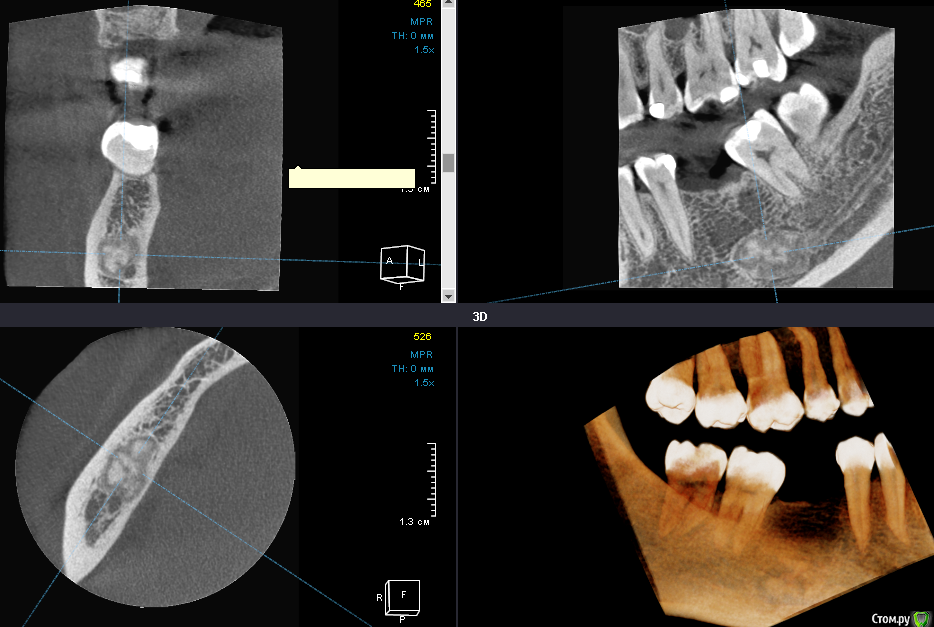

gum Опубликовано 24 октября, 2018 Поделиться Опубликовано 24 октября, 2018 (изменено) Коллеги здравствуйте. Пациент обратился с целью имплантации в области 46. На снимке новообразование. Что это и как поступить? Возможно типа одонтомы, так как видны структуры напоминающие фрагменты зубов. Изменено 24 октября, 2018 пользователем gum Ссылка на комментарий

___49___ Опубликовано 24 октября, 2018 Поделиться Опубликовано 24 октября, 2018 (изменено) Доброго. Похоже на одонтому , в ЧЛХ не хотите направить ? Какой анамнез, что с чувствительностью в области губы ,состояние регионарных лимфоузлов? Изменено 24 октября, 2018 пользователем ___49___ Ссылка на комментарий

Дмитрий Л. Опубликовано 24 октября, 2018 Поделиться Опубликовано 24 октября, 2018 Наверное, здесь лучше мост) Или имплантат в обход одонтомы. Ну а саму одонтому наблюдать. 1 Ссылка на комментарий

gum Опубликовано 25 октября, 2018 Автор Поделиться Опубликовано 25 октября, 2018 Думаете не стоит ее убирать?Имплантат не вариант при одонтоме. 1 Ссылка на комментарий

Дмитрий М Опубликовано 25 октября, 2018 Поделиться Опубликовано 25 октября, 2018 Думаете не стоит ее убирать?Имплантат не вариант при одонтоме.подержу, имплант ставить или удалять риск, т.к. не предсказуемая динамика, и технически сложно, риск перелома. Ссылка на комментарий